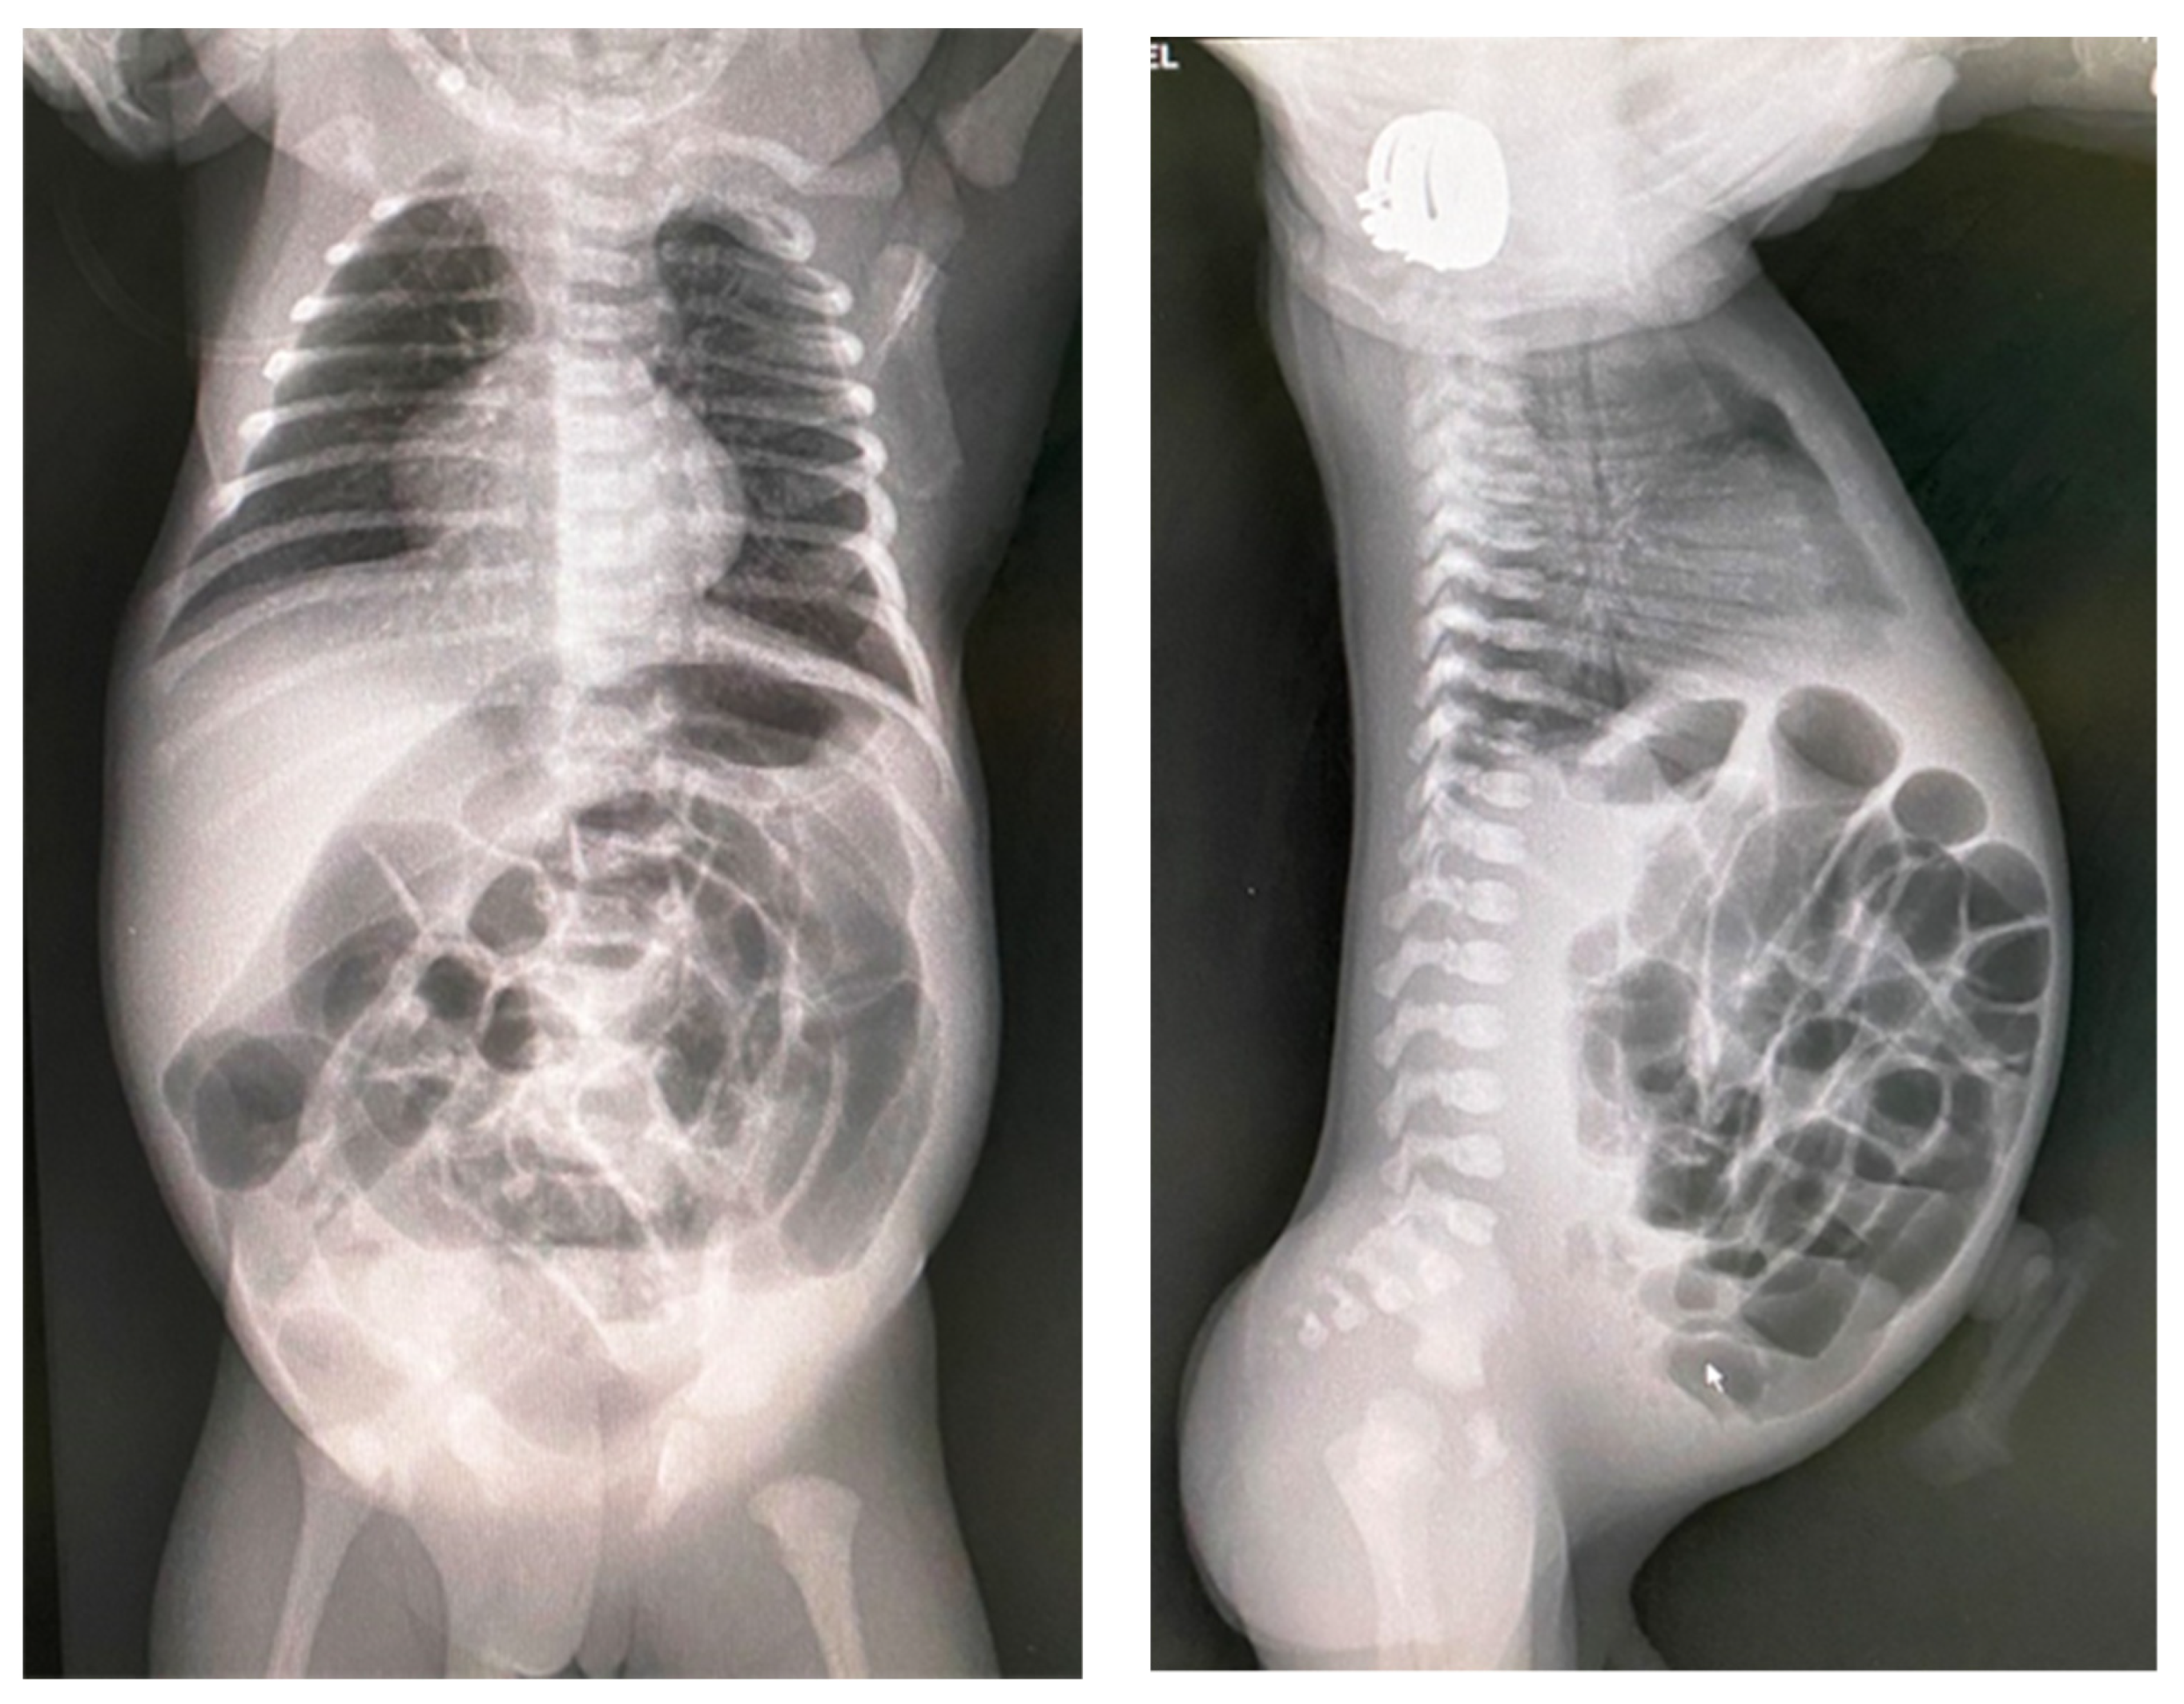

These clinical manifestations will raise the suspicion of cystic fibrosis and investigations will be continued with thoracoabdominal X-ray, ultrasound, genetic investigations, and sweat test. The ultrasound may show pseudo-thickening of the bowel walls because of thick and adhesive meconium. Stratified and dehydrated meconium causes the bowel lining to have increased echo intensity. Intestinal gases cannot be eliminated due to the high density of meconium and its adhesion to the intestinal walls, so that the abdomen becomes intensely weathered, occlusive, but in the absence of air–fluid levels. The abdominal radiograph has almost the same appearance in the supine and erect position with distended loops without air–fluid levels and a ground glass or ‘soap-bubble’ appearance (Neuhauser’s sign) (Figure 3). Another typical occurrence on X-ray is inspissated pellets along the large intestine wall. If there is a total obstruction, there might not be any air in the rectum.

Figure 3.

Abdominal X-ray showing dilated intestinal loops and a ground glass appearance; antero-posterior incidence and profile incidence.